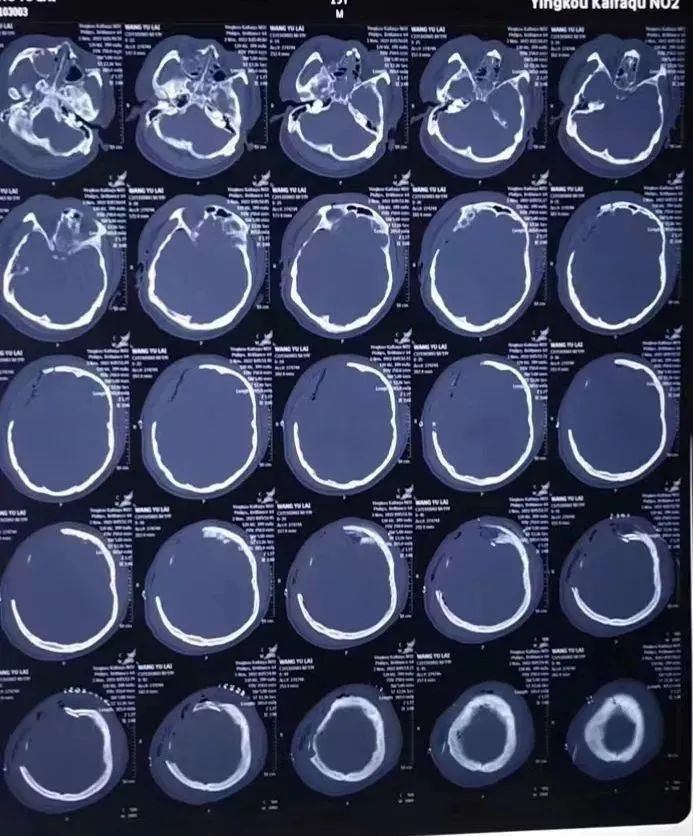

(治疗后影像报告)

一周后,患者神志完全清醒。一个月后经过局部血肿引流术后,头痛症状明显缓解,现已顺利出院。

(术前影像报告)

(术后影像报告)

(颅骨修补术前后对比图)